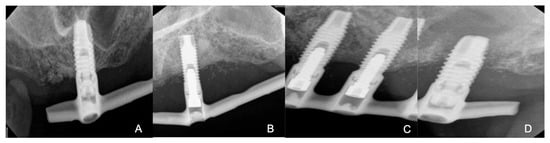

2. Case Presentation